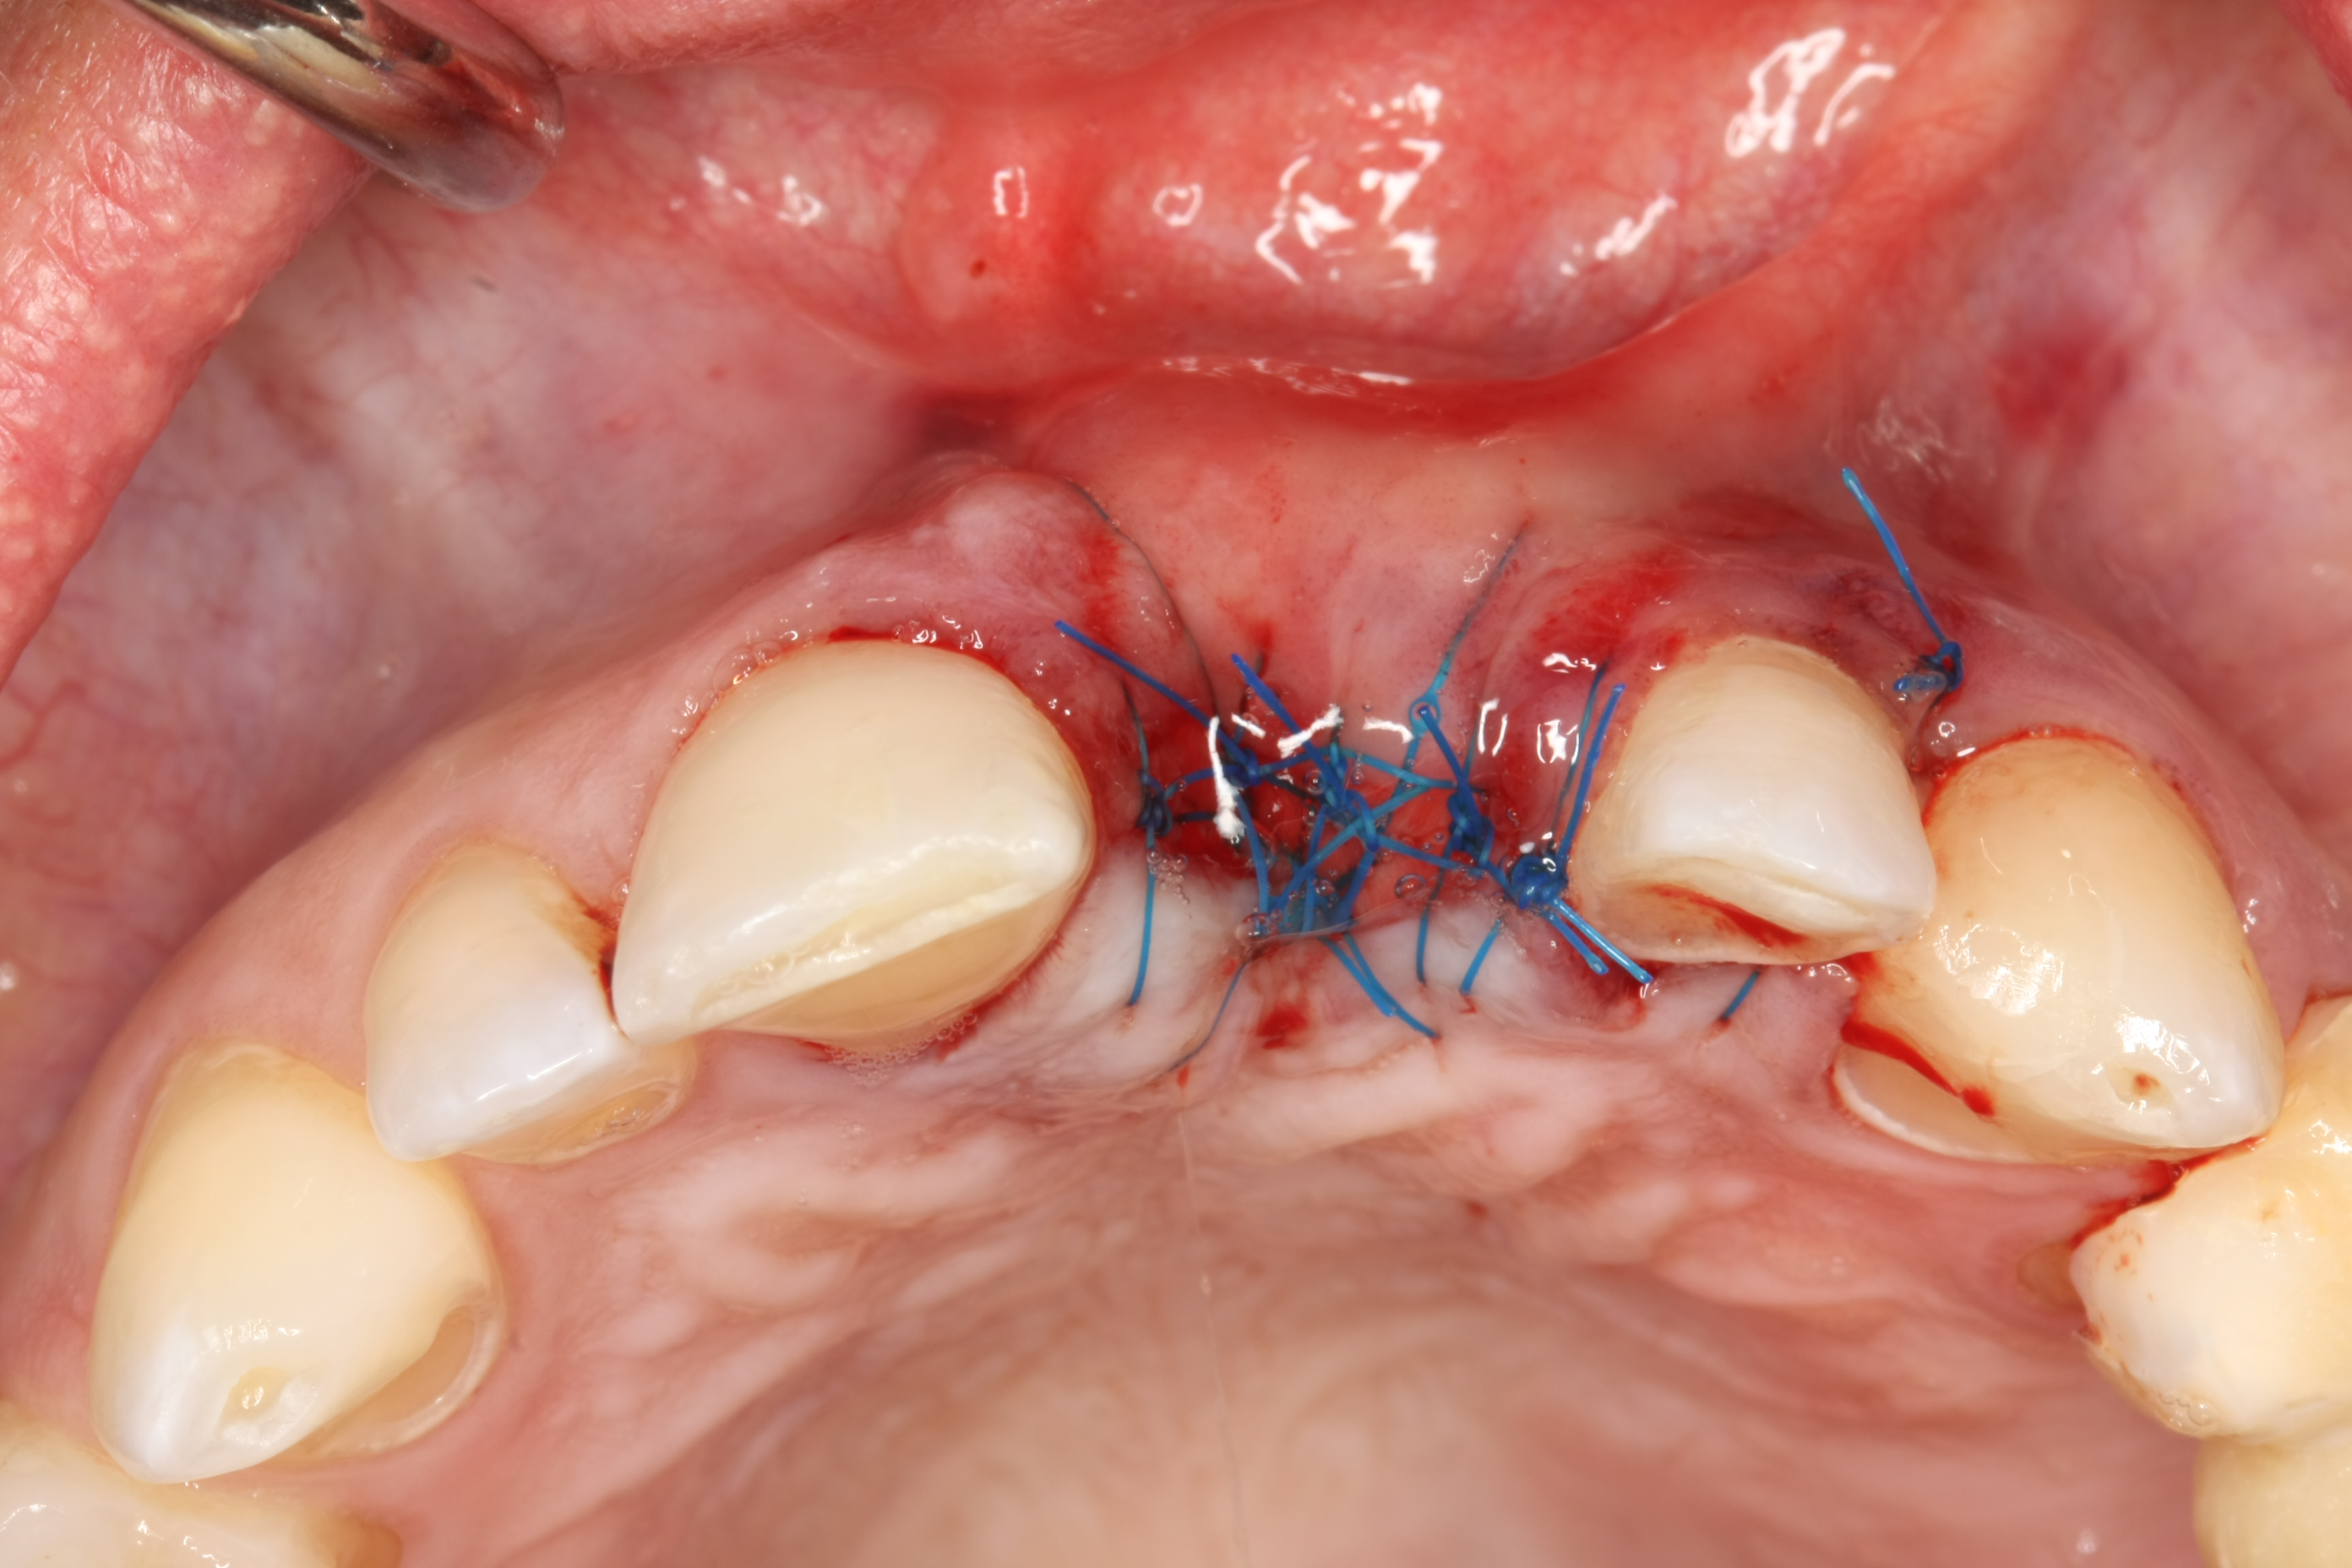

Image C2:5 8 Days Post-Extraction

Occlusal view: Rapid wound healing & re-epithelisation.